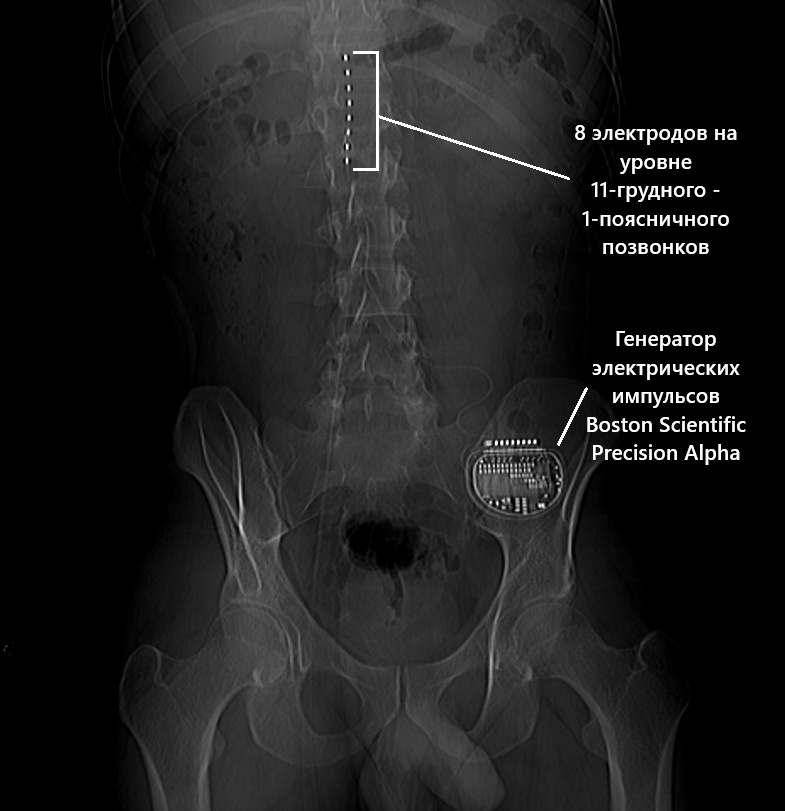

Клинический случай: рентгенограмма позвоночника у пациента с электронейростимулятором

Перед вами результаты рентгенографии позвоночника пациента с установленным нейростимулятором Boston Scientific. Эти электроды вдоль спины помогают справиться с болью, которую не берут обычные методы.

Работает так: прибор посылает импульсы, которые «перебивают» болевые сигналы. В результате боль отступает.